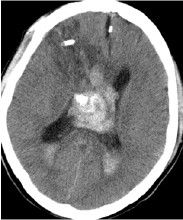

CT掃描見腫瘤位於一側腦室內或位於透明膈在腦室內邊界清楚呈圓形等密度或略高而不均勻密度影半數以上腫瘤有點狀鈣化,當鈣化灶較大時X線平片也可見到。幕上中樞神經細胞瘤增強後腫瘤有中度至明顯強化MRI成像優於CT,對腫瘤範圍及所處部位有診斷價值可見多數腫瘤與透明隔或側腦室壁有關。腫瘤實質部分T1W為等或稍高信號,T2W為高信號,瘤內可見血管流空影。部分腫瘤常伴有出血靜脈注入順磁性顯影劑後,可見輕度增強腫瘤與側腦室壁或透明膈相附著(圖1)。